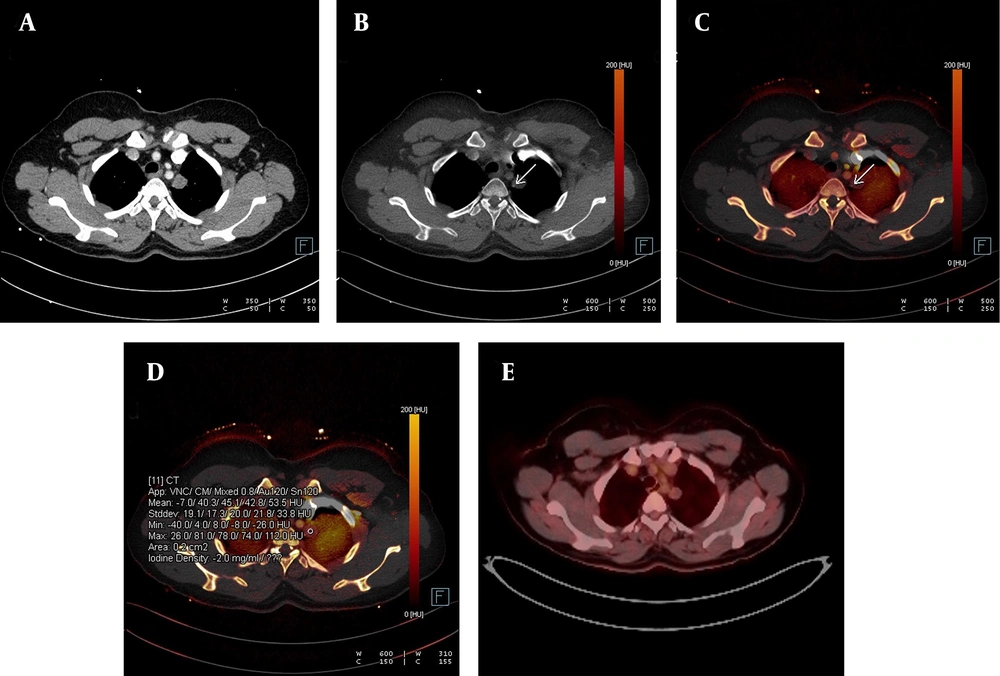

Detection of calcification in a lung nodule on a virtual non-contrast-enhanced image in dual-energy computed tomography, DECT. A, The weighted average image of the lesion in the apical segment of the left lung; B, The virtual non-contrast-enhanced image showing a small calcification around the nodule (white arrow); C, Dual view; and D, Iodine load are shown; E, No significant 18-FDG uptake was observed in the PET-CT images obtained from the same patient.